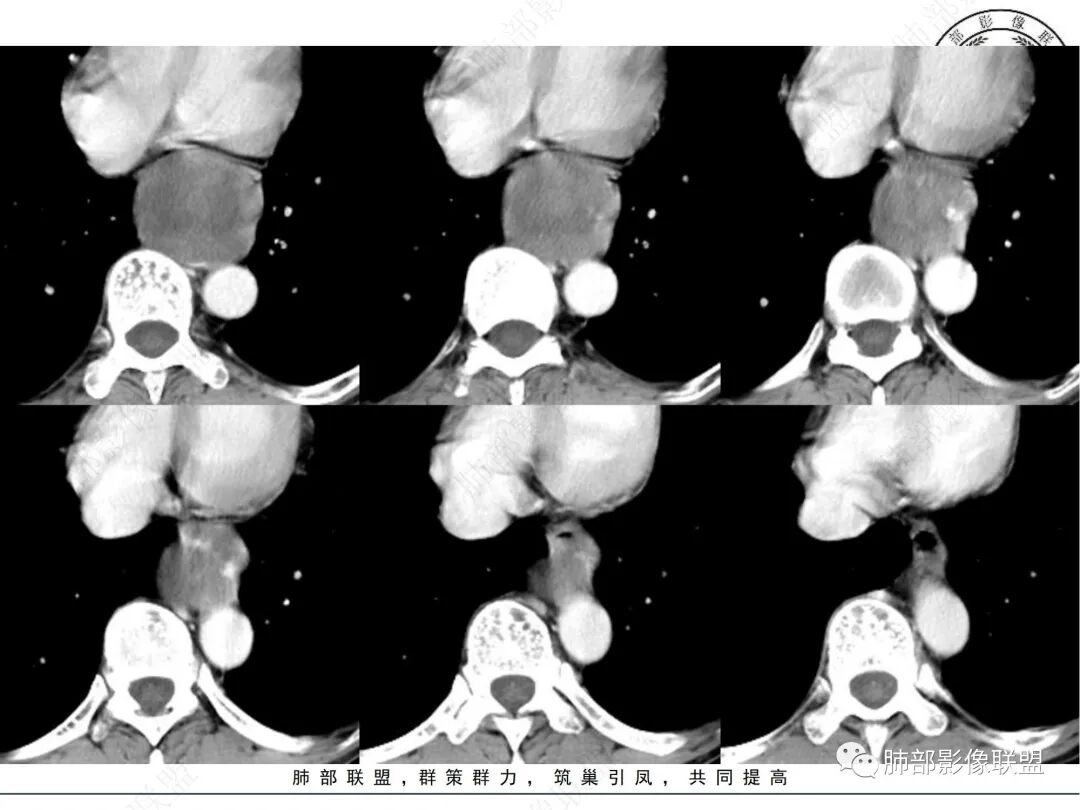

临床:中老年男性,体检发现后纵隔占位,

影像表现:后纵隔类圆形软组织肿块,增强扫描不均匀强化,内部可见囊变区及实性区,实性区明显延迟强化,边界清晰,邻近左心房及食管受压改变,

定位定性:后纵隔良性肿瘤,

诊断:神经源性肿瘤,神经鞘瘤

1. 中老年男性,偶然发现后纵隔占位(没有吞咽梗阻等消化道症状)。实验室检查无特殊。

2. 后纵隔类圆形囊实性占位,整体圆张力大,边界光整,增强后不均匀强化(似乎形成AB区?),轻度强化囊性区明显强化实性区,病灶边缘有明显强化血管影,与食道前壁界限不清,且食道明显受压,主动脉血管受压有脂肪间隙。考虑神经源性肿瘤,神经鞘瘤的可能。